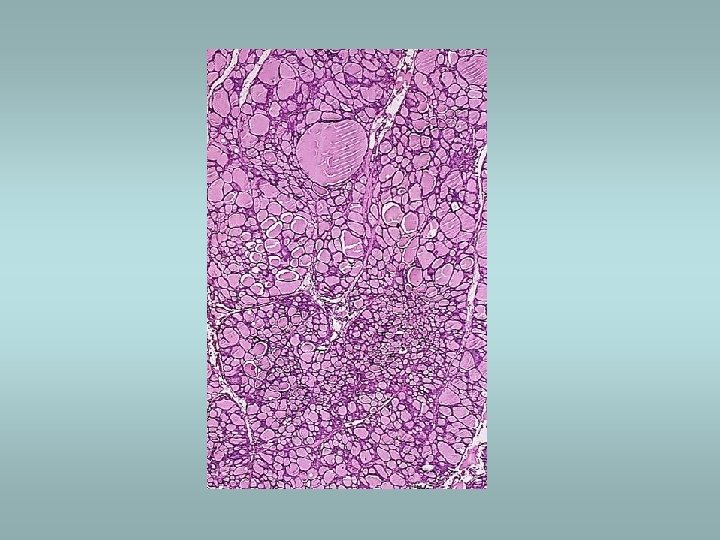

Hashimoto’s thyroiditis ü Autoimmune disorder ü Female predominance ü Defect in suppressor T cells, production of autoantibodies ü Associated with other autoimmune disease (SLE, Sjögren sy, rheumatoid arthritis…) ü Microscopically – dense lymphocytic infiltrate, germinal centers, abundant eosinophilic oncocytes (Hürtle cells)

Tumors Benign – adenomas ü Well demarcated ü Fibrosis ü Haemorrhage ü Calcifications ü Hürtle cell adenoma - oncocytic ü Usually „cold“ Malignant - carcinomas ü See transparency